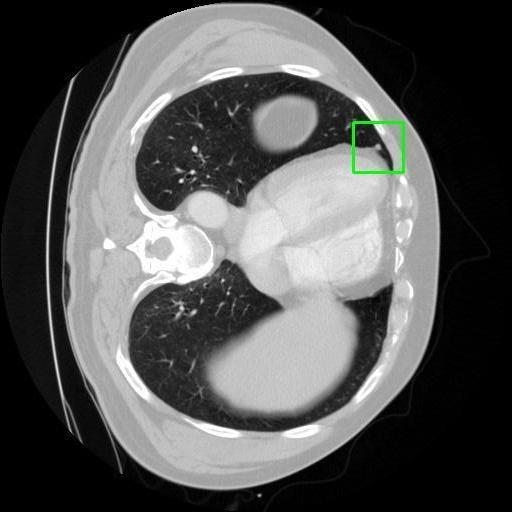

We developed an AI-based system using deep learning models for analyzing lung CT scans to detect and classify pulmonary nodules. We chose the YOLOv11 architecture for its enhanced object detection capability and adapted it specifically for medical imaging, incorporating pixel-level precision and severity classification.

Classification into three severity levels with colored bounding boxes.

Maintaining performance on small, complex features like micro-nodules tested the limits of traditional object detectors.

Successfully built and deployed an AI model (YOLOv11) capable of detecting lung nodules in CT scans with high accuracy and real-time performance.

Designed a severity classification system that categorizes nodules into null, moderate, and severe using colored bounding boxes, assisting in rapid clinical decision-making.